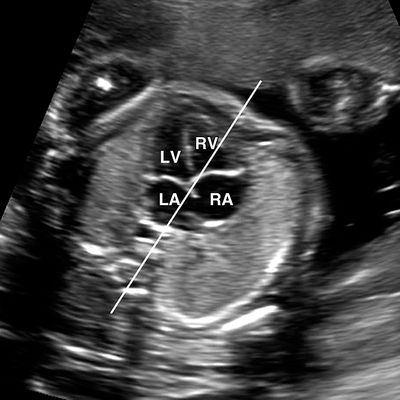

A fetal echo, also known as fetal echocardiography, is a specialized ultrasound procedure performed at Dr. Chawla's Diagnostics in Delhi to thoroughly assess the structure and function of an unborn baby's heart. This non-invasive test uses sound waves to create detailed images of the fetal heart, helping our expert cardiologists detect any potential congenital heart defects or abnormalities before birth. We offer advanced fetal echo services in a comfortable and reassuring environment.

The fetal echo procedure is similar to a routine pregnancy ultrasound. You'll lie comfortably on an examination table, and a trained sonographer will apply a gel to your abdomen. A transducer will be moved across your skin to create images of the baby's heart. The scan is painless and generally takes between 30 to 60 minutes. Our experienced specialists in fetal echocardiography in Delhi will ensure your comfort and provide clear communication throughout the process.